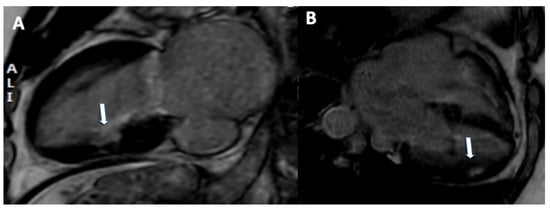

A representative case has shown in Figure 5.

Figure 5.

A 45-year-old patient with history of myocardial infarction. Subendocardial late gadolinium enhancement was observed in inferior (arrow, (A)) and inferolateral (arrow, (B)).